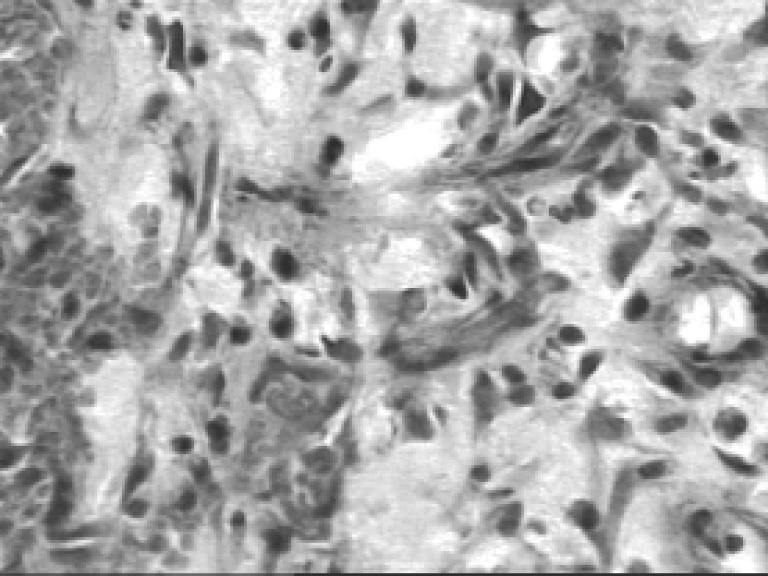

Вокруг сосудов происходит формирование лейкоцитарного инфильтрата, утолщение эпидермального валика по периметру раны, увеличение ядра клеток (рис. 3). В области сосудов кожи определяются грануляционная соединительная ткань и миграция нейтрофилов в зону дефекта.

Рис. 3. Микропрепарат мягких тканей в области раны бедра крысы через 3 суток после РМП. Окраска гематоксилином и эозином, ув. ×250

В течение первых трех суток после РМП отмечались начальные признаки регенерации в виде появления под струпом активированных фибробластов, синтезируемых ими структурных белков и межуточного вещества соединительной ткани.